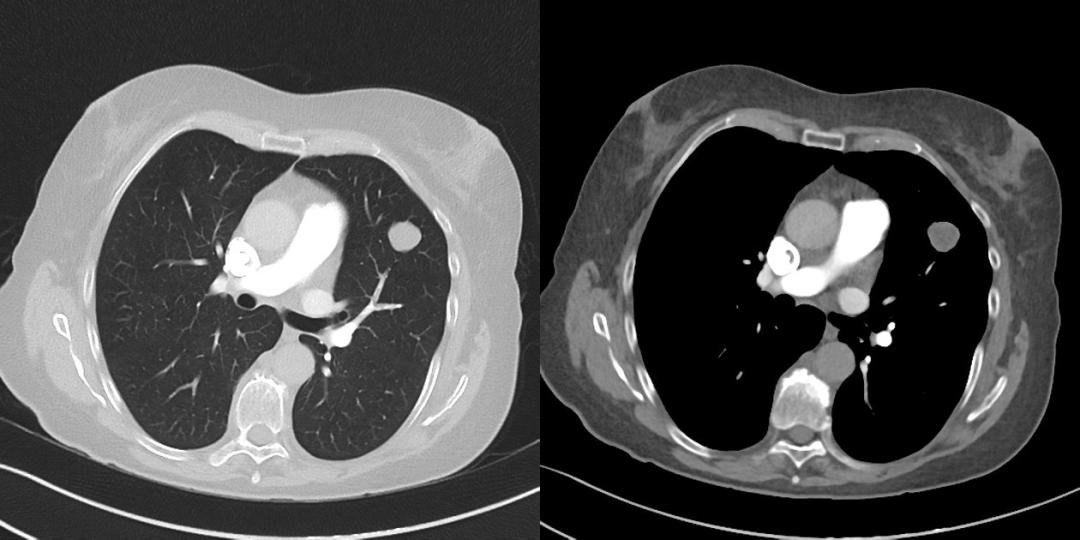

女性 13 岁 因发热、胸闷一周入院检查;一周前受凉发热后出现发热,最高体温达 38.4°,伴活动后胸闷,休息片刻可缓解;胸部 CT 平扫+增强图像如下;

患者 13 岁小孩 女性 因发热入院,发现右肺上叶近肺门处椭圆形肿块,密度相对均匀,增强扫描未见明显强化,这种影像表现我们可以考虑哪些疾病呢?我相信第一个就会考虑支气管囊肿,因为病灶椭圆形、边界清晰,没有强化,从影像表现上来看,确实首先应该考虑。